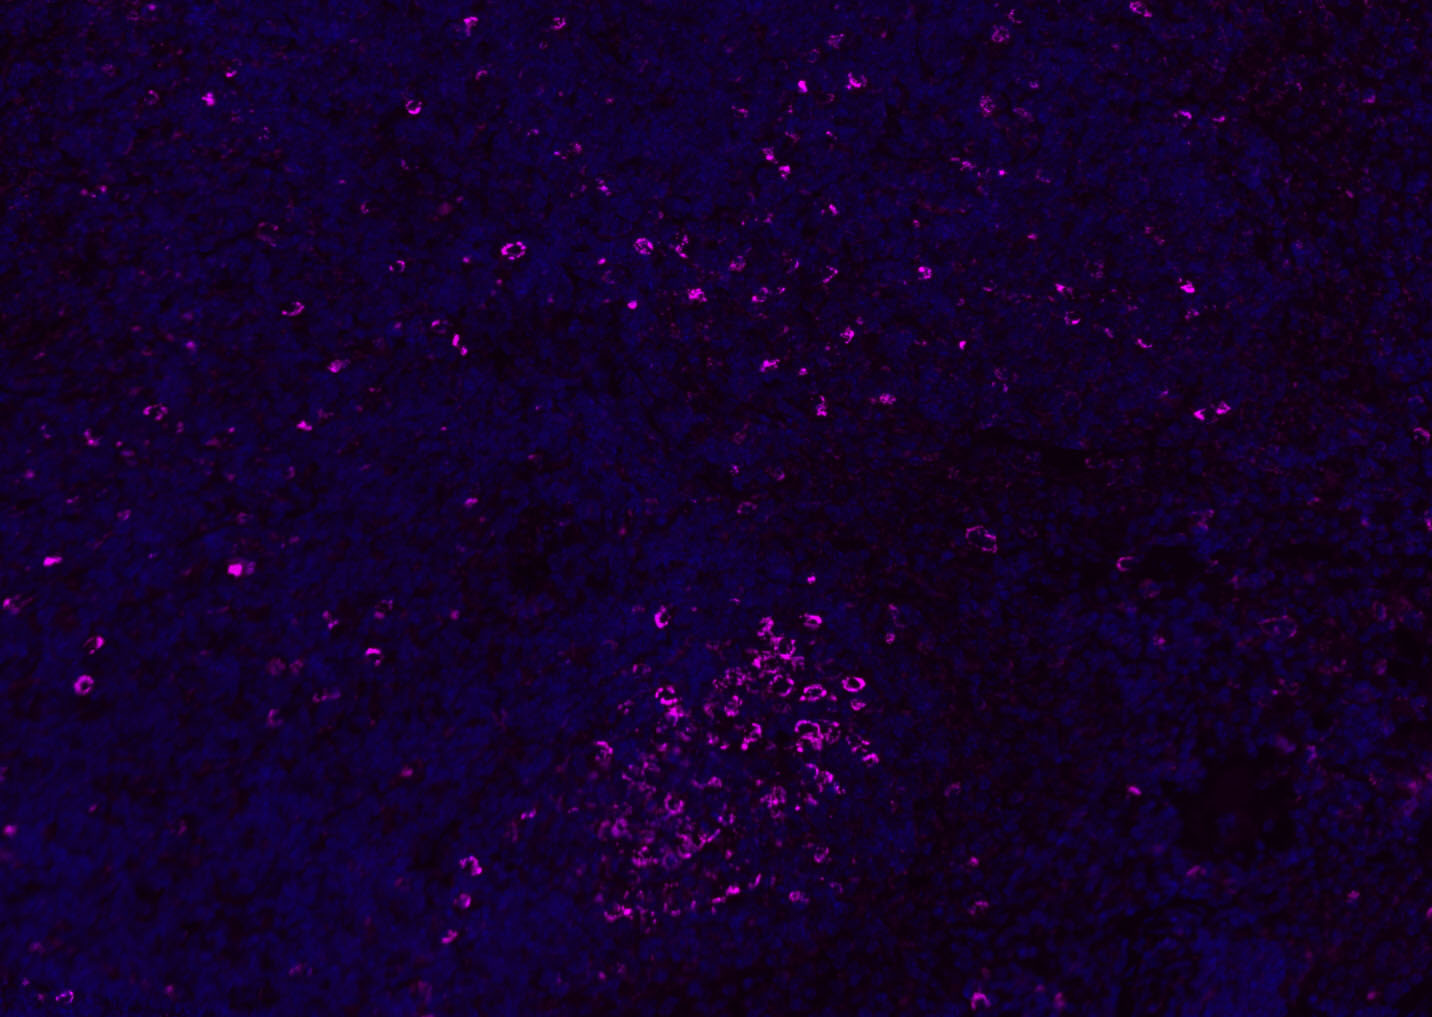

Paraformaldehyde-fixed, paraffin embedded (Rat lymphoid); Antigen retrieval by boiling in sodium citrate buffer (pH6.0) for 15min; Blocking buffer (normal goat serum) at 37°C for 30min; Antibody incubation with (CD8B) Polyclonal Antibody, Unconjugated (bs-4914R) at 1:100 overnight at 4°C, followed by a conjugated Goat Anti-Rabbit IgG antibody (bs-0295G-AF647) for 90 minutes, and DAPI for nuclei staining.